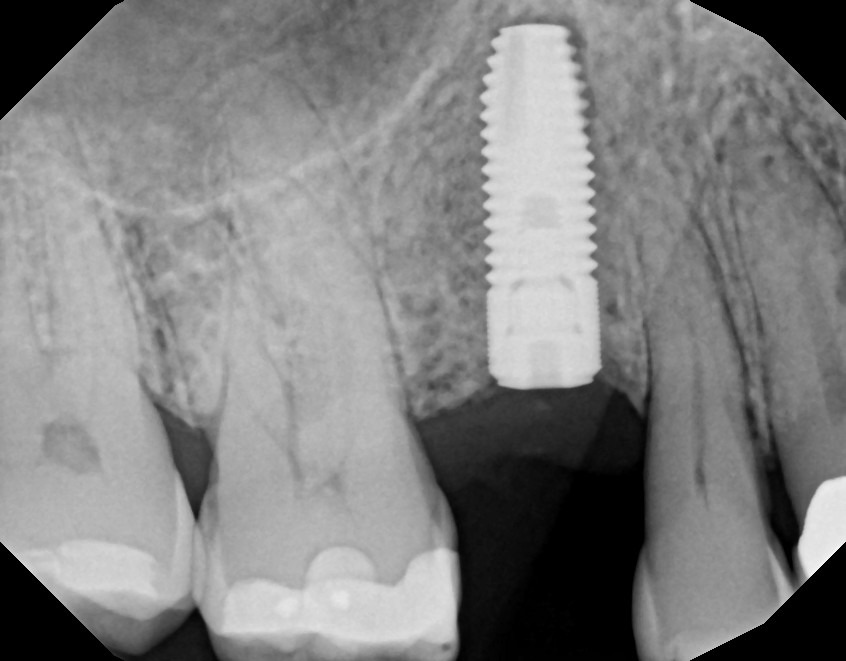

A dental implant is a permanent solution for replacing missing teeth by surgically placing a titanium post into the jawbone. This post acts as an artificial tooth root and provides a strong foundation for a crown, bridge, or denture. Over time, the implant integrates with the bone through a process called osseointegration, ensuring stability and durability. Dental implants restore function, improve appearance, and help maintain jawbone health by preventing bone loss. With proper oral hygiene and regular dental visits, implants can last for many years.